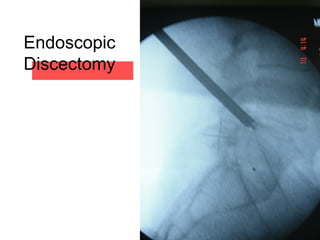

Endoscopic

Discectomy